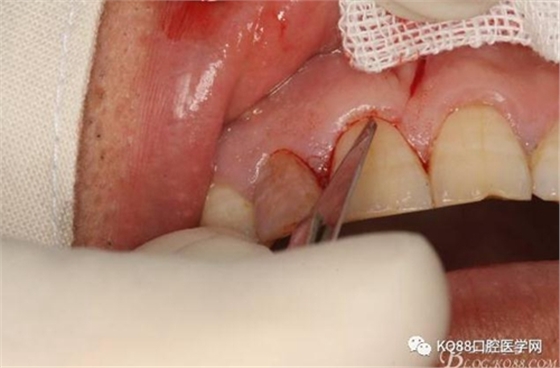

圖7. 角形切口中的齦溝內(nèi)切口情況:11號(hào)刀片伸進(jìn)齦溝內(nèi)斜切。

圖8.從垂直切口和水平切口的連接處翻瓣。發(fā)現(xiàn)11和12之間的骨壁有缺損。